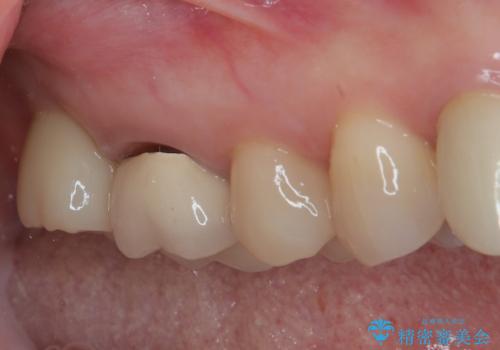

残念ながら歯冠から歯根に向かって破折が認められたため、患者様了解のもと、抜歯してインプラントの即時埋入を行いました。

インプラントと骨の安定程度を測定したところ、十分な数値が得られたため、速やかに仮歯を装着して咬合回復をさせることができました。

抜歯を含めた外科処置を1回に抑えることができ、あっという間に治療を終えることができました。